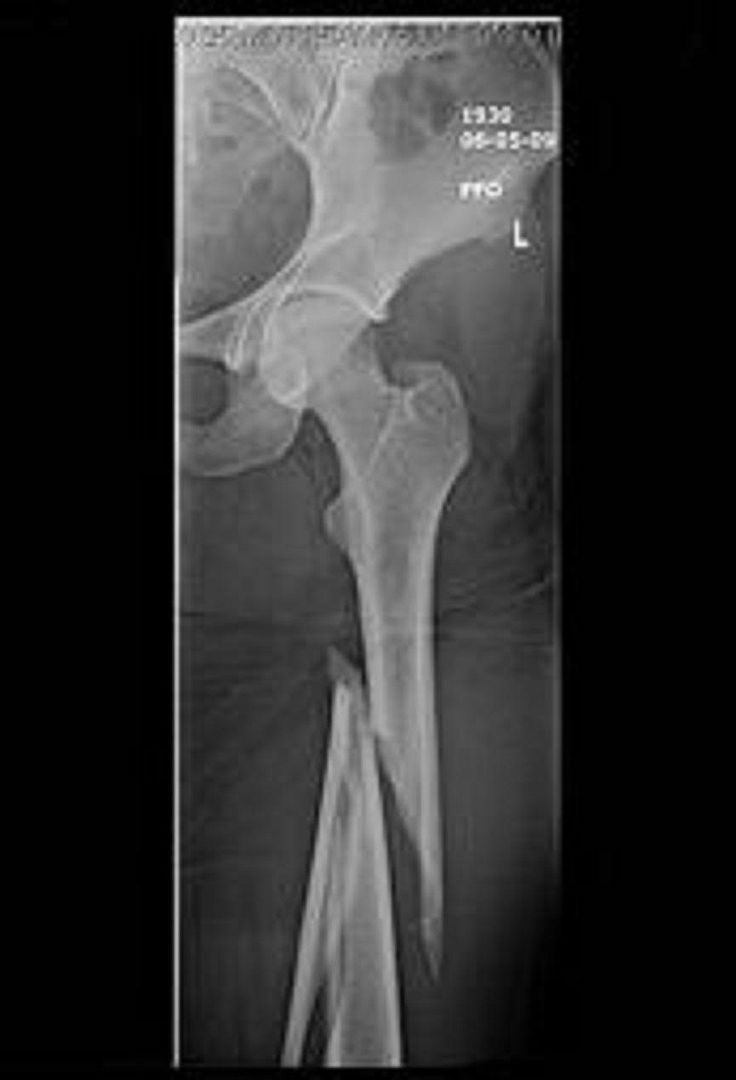

Spiral Fracture of the Femur Musculoskeletal Case Studies CTisus CT

Femoral diaphyseal spiral fracture in 22 month old What Causes A Spiral Fracture Of The Femur For a femur to break, excessive force needs to be applied to it. a spiral fracture is a bone fracture that occurs when a long bone is broken by a twisting force. A spiral fracture is a complete break in a bone that is caused by a twisting motion or force. what causes a broken femur? The break. What Causes A Spiral Fracture Of The Femur.